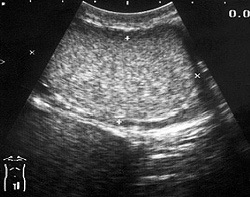

Иногда диагностика острого орхита затруднена вследствие реактивной водянки яичка или периорхита. В сомнительных случаях проводится ультразвуковое сканирование и биопсия яичка. При подозрении на абсцесс яичка выполняют диагностическую пункцию и ультразвуковое исследование, подтверждающее наличие жидкого содержимого.